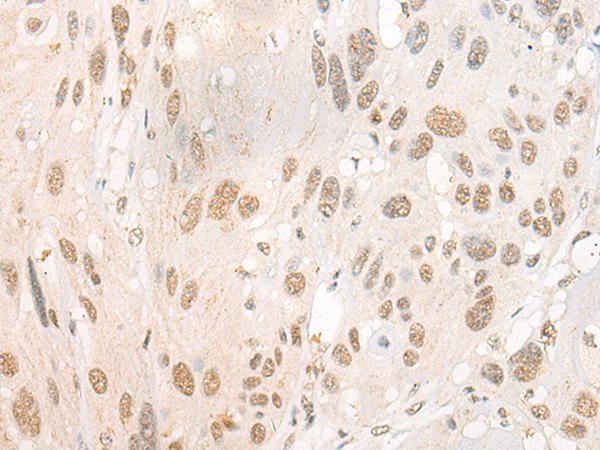

分类: 科研抗体货号: P07679别名: RNF84; MGC:39780应用: IHC反应种属: Human, Mouse